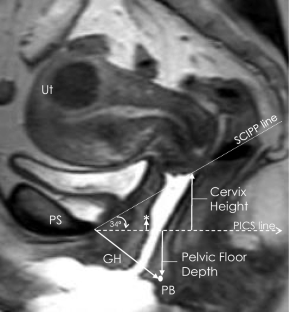

A case–control study was conducted from June 2017 to August 2018 comparing two groups of nulliparous women: <40 years old and ≥ 70 years old. Clinical evaluation included POP-Q, instrumented speculum testing, and handgrip strength. Dynamic 3D-stress MRI was performed on all women to obtain genital and levator hiatus (LH) lengths, LH area, and levator bowl volume. LH shape was quantified using a novel measure called the “V-U index.” Pubovisceral muscle (PVM) cross-sectional area (CSA) was also measured. Bivariate comparisons between the two groups were made for all variables. Effect sizes were calculated for MRI measurements.

Betschart C, Chen L, Ashton-Miller JA, Delancey JO. On pelvic reference lines and the MR evaluation of genital prolapse: a proposal for standardization using the pelvic inclination correction system. Int Urogynecol J. 2013;24(9):1421–8. https://doi.org/10.1007/s00192-013-2100-4.

Chen L, Lisse S, Larson K, Berger MB, Ashton-Miller JA, DeLancey JO. Structural failure sites in anterior vaginal wall prolapse: identification of a collinear triad. Obstet Gynecol. 2016;128(4):853–62. https://doi.org/10.1097/AOG.0000000000001652.

Sammarco AG, Nandikanti L, Kobernik EK, Xie B, Jankowski A, Swenson CW, et al. Interactions among pelvic organ protrusion, levator ani descent, and hiatal enlargement in women with and without prolapse. Am J Obstet Gynecol. 2017;217(5):614 e611–7. https://doi.org/10.1016/j.ajog.2017.07.007.